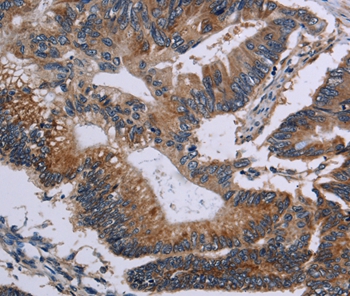

Immunohistochemical analysis of paraffin-embedded Human colon cancer tissue using #35692 at dilution 1/50.

应用详情:Immunohistochemistry: 1:50-1:200